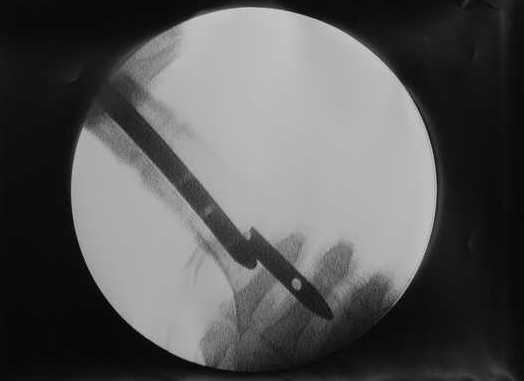

27 марта выполнено удаление блокирующих винтов (сломанный винт пришлось высверливать цапфен-бором), сломанного штифта (дистальный фрагмент удален через канал, образованный разверткой из коленного сустава - image 4),